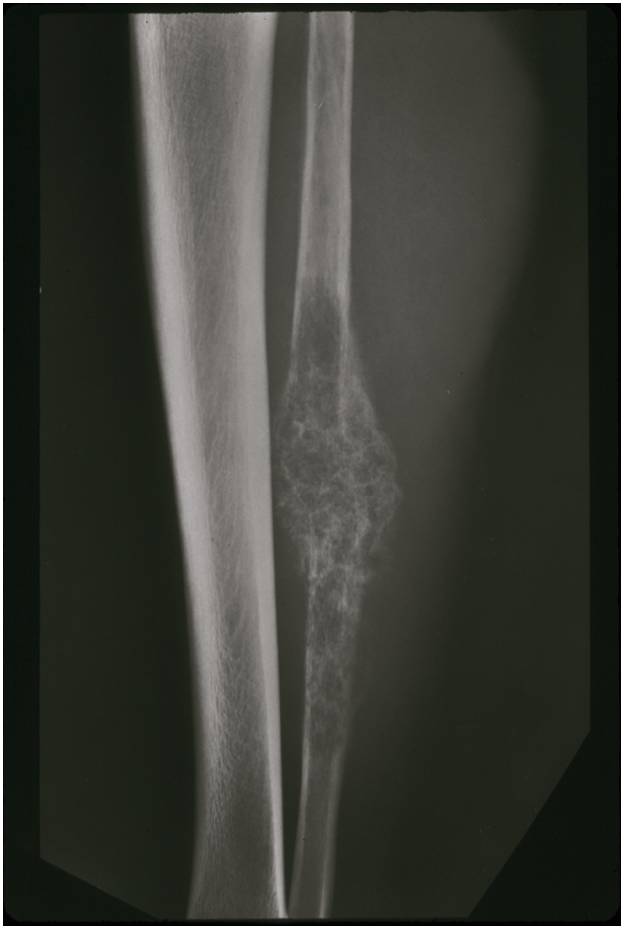

Radiographic Presentation

- Aggressive motheaten to permeative lesion

- Indistinct border in most cases

- Osseous destruction with a soft tissue component

- Chondroid matrix calcification may be present (60-70% of cases)

- Soft tissue mass